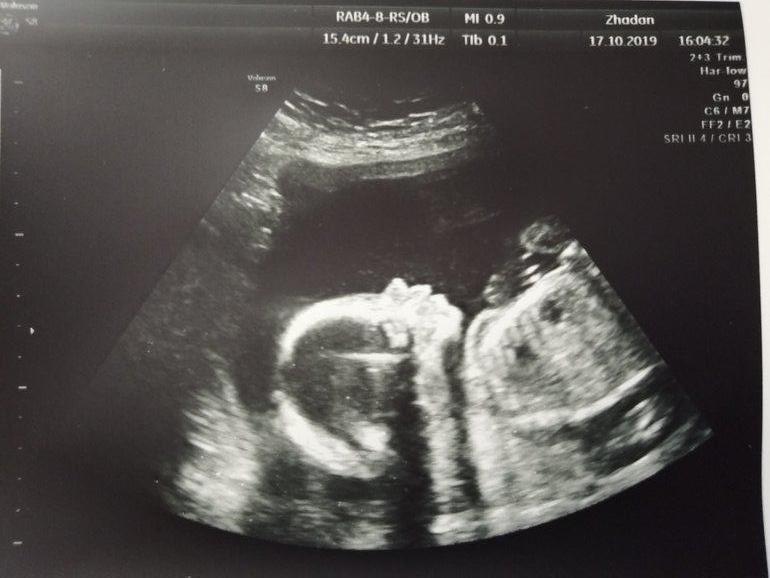

Теперь без сомнений подтвердили нам самую красивую и главное здоровую ДЕВОЧКУ! У нас будет доча! Папа рад очень, бабушки довольны, все в восторге! Ну а я радуюсь, что всё правильно сформировалось и развивается!

Поздравляю с принцессой!) ничего себе как на 2ром скрининге все видно, и носопырочку и губки. Аааа, милота) тоже хочу, быстрей бы понедельник))

Видно всё до мелочей! Кулачки во рту, пальчики, пяточки с пальчиками 3см

попка ))) личико, все косточки ... Уже полноценный ребенок, но пока малюсенький. Понедельник вообще не за горами )))) счастливой вам встречи с малышариком!